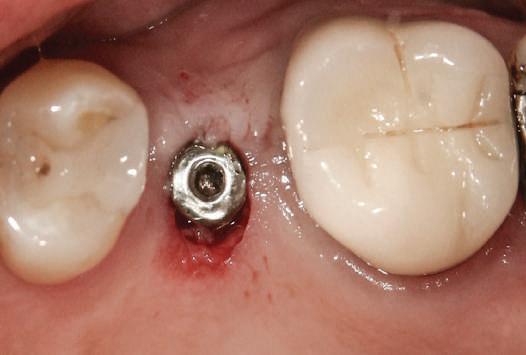

Şapte luni mai târziu (fig. 2), acele bonturi individualizate din prima etapă au manifestat semne de recesie de 1-3mm. Atitudine: S-a decis reprepararea intraorală a tuturor bonturilor (fig. 3), astfel încât toate marginile bonturilor să fie la nivelul sau sub marginea gingivală (de notat că 1.1. şi 2.1. au fost submersaţi ulterior pentru a avea sprijin implantar deplin).

Cazul (1): Reprepararea intraorală a bonturilor Figurile

2. După 7 luni, bonturile individualizate din prima etapă au prezentat recesie de 1-3mm.

3. Bonturile repreparate intraoral.